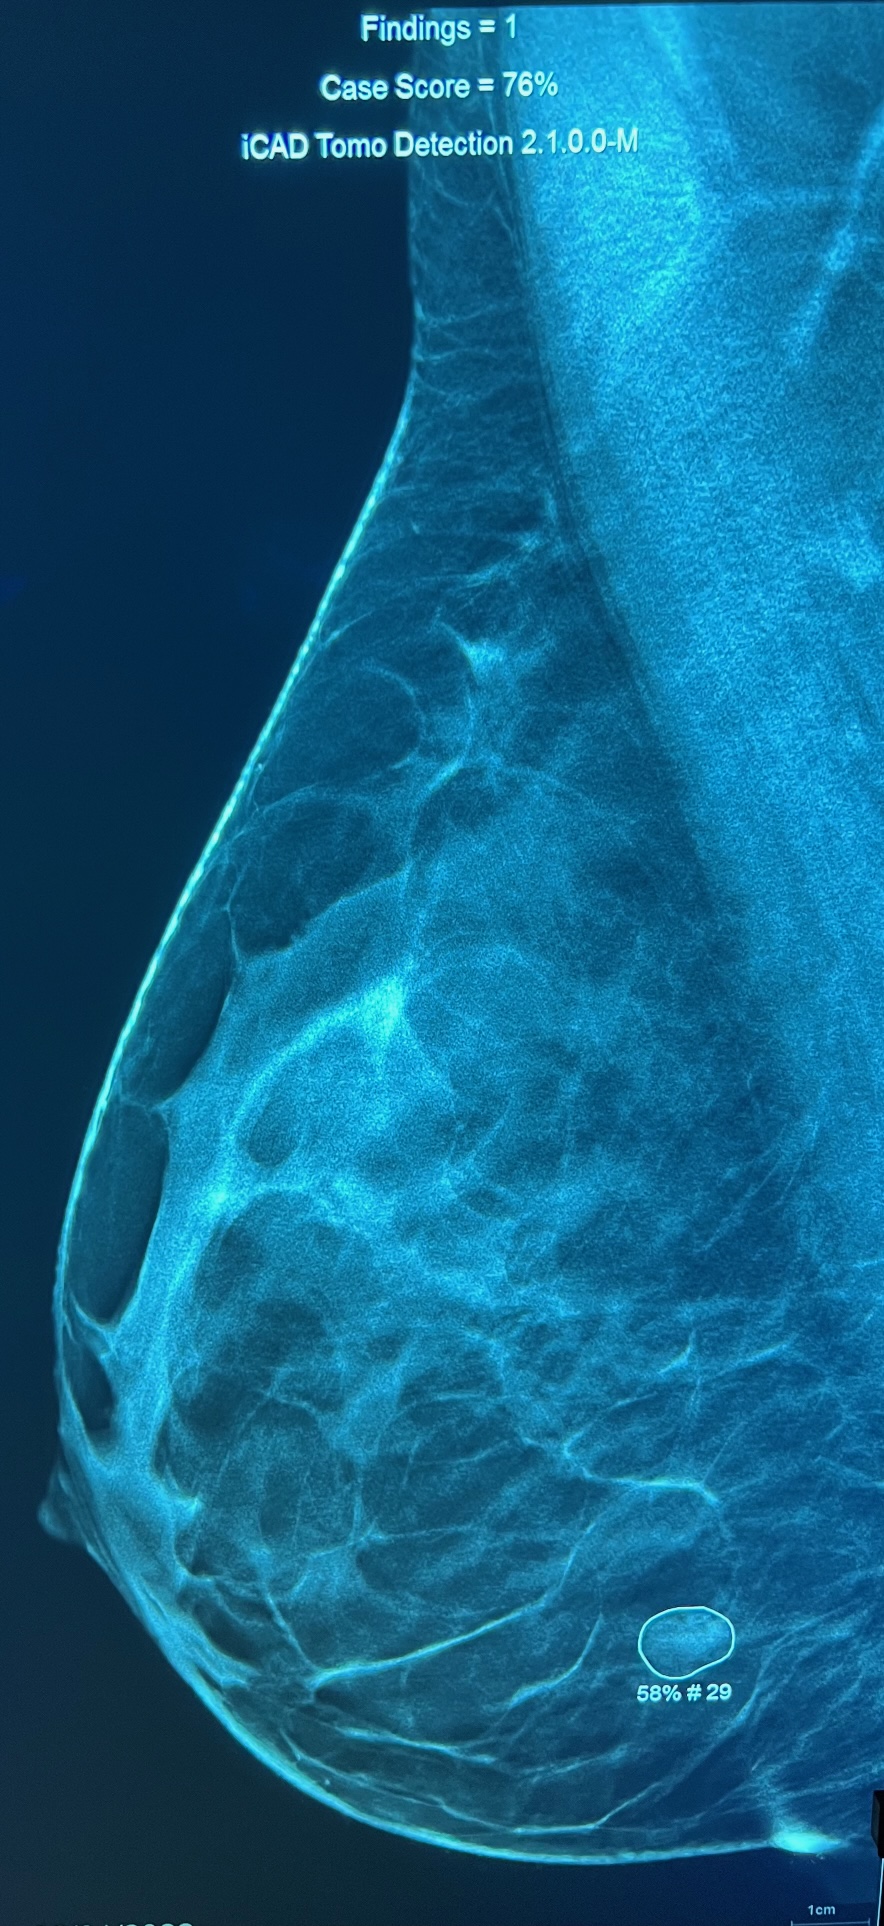

Le radiologue lit votre mammographie et dans un second temps utilise sur le mammographie numérique un CAD (computed aided detection), de dernière génération (ICAD pour imagerie 2D et tomosynthèse 3D) qui va marquer les micro-calcifications (marquées par un carré) et les masses (marquées par un rond) avec la valeur prédictive positve en faveur d'une lésion maligne.

Micro-calcifications (carré) Petite masse, distorsion architecturale (rond)

Valeur prédictive de lésion maligne 58%